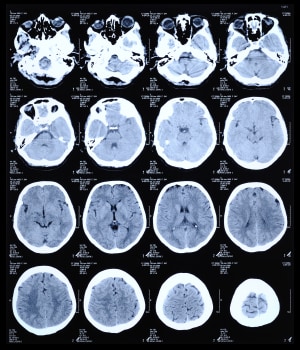

Computed Tomography

One two-dimensional x-ray image does not tell you much, but computed tomography takes scores of them and knits them together with a computer to generate a high-resolution 3D image.

CT is one of the two technologies that utilize ionizing radiation to create a picture of what is going on inside the body. At its simplest, a CT scan is an x-ray slice of the body. Slices are repeated along the area of interest, although for performance reasons multiple slice transmitters/receivers are typically grouped next to each other. The body can also be moved during exposure in order to create a “spiral” image that can be unwound into slices or a 3D view (see Figure 1).

Figure 1: CT scan of the human brain.